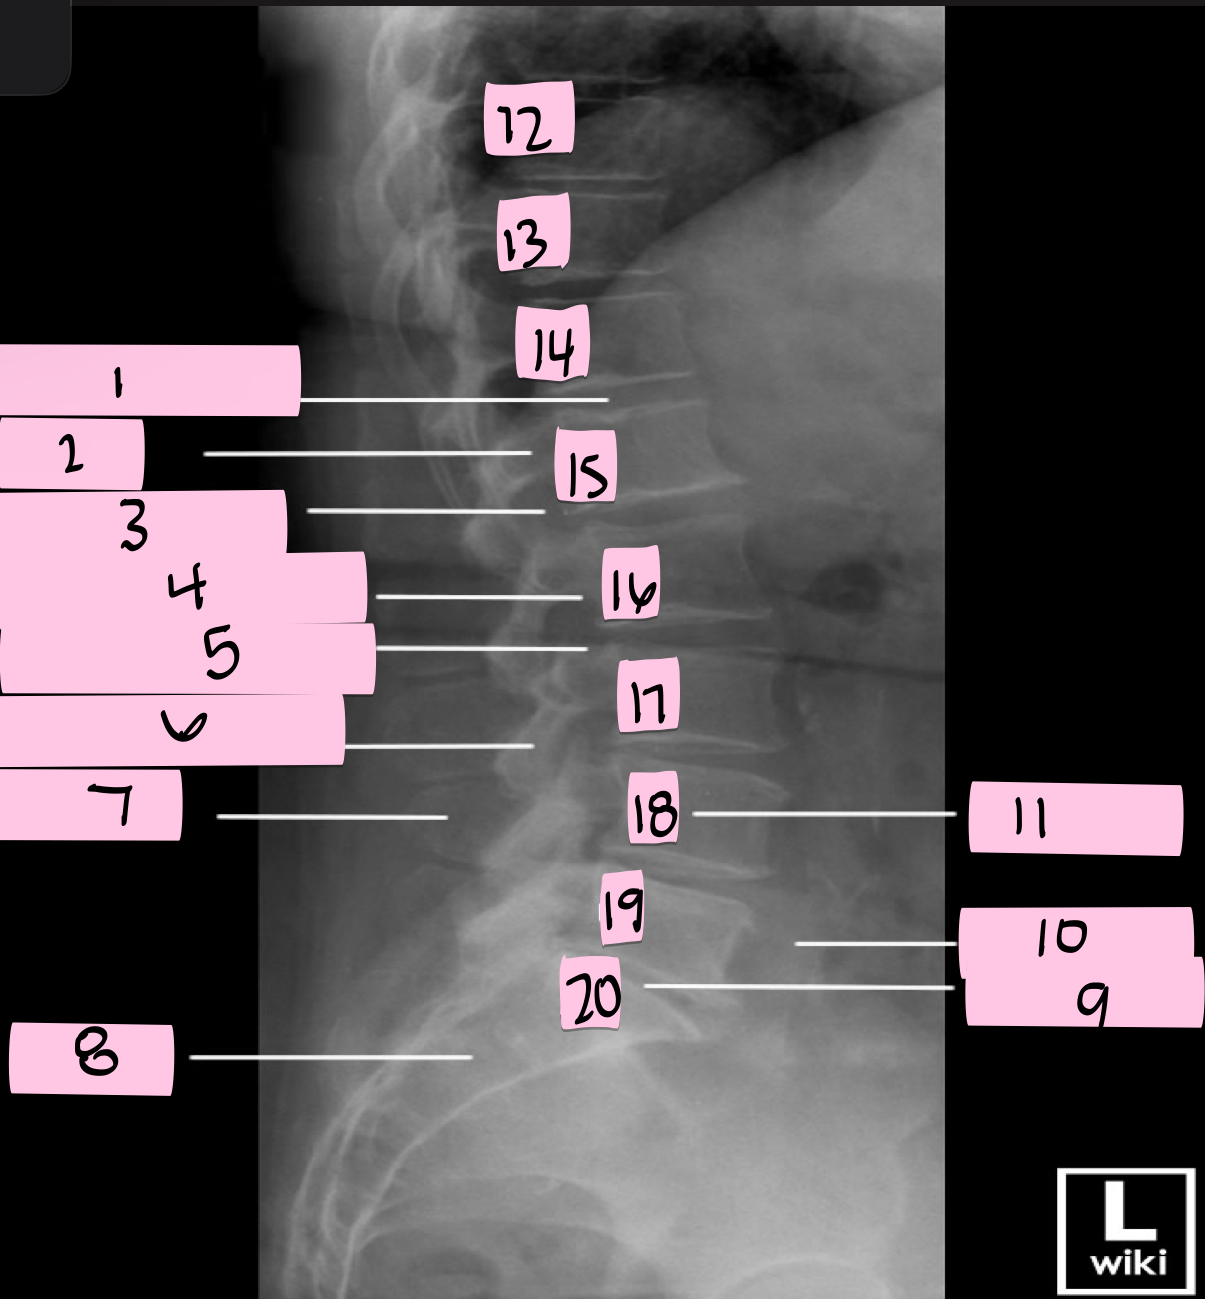

What is 1 pointing to?

Intervertebral disk

What is 2 pointing to?

Pedicle

What is 3 pointing to?

Intervertebral foramen

What is 4 pointing to?

Inferior vertebral notch

What is 5 pointing to?

Superior vertebral notch

What is 6 pointing to?

Inferior articular process

What is 7 pointing to?

Spinous process

What is 8 pointing to?

Sacrum

What is 9 pointing to?

L5 S1 joint

What is 10 pointing to?

Iliac crest

What is 11 pointing to?

Vertebral body (L4)

What is 12 pointing to?

T10

What is 13 pointing to?

T11

What is 14 pointing to?

T12

What is 15 pointing to?

L1

What is 16 pointing to?

L2

What is 17 pointing to?

L3

What is 18 pointing to?

L4

What is 19 pointing to?

L5

What is 20 pointing to?

S1